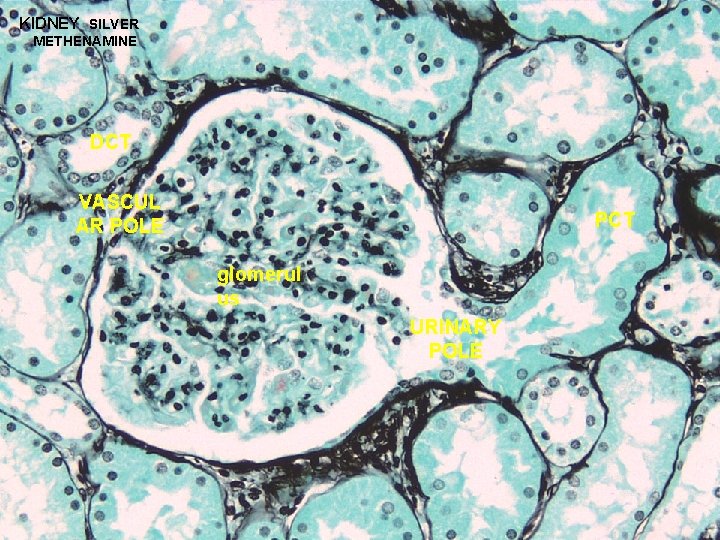

URINARY SYSTEM RENAL CORPUSCLE BOWMAN’S CAPSULE + GLOMERULUS FILTRATION APPARATUS OF KIDNEY 1. BOWMAN’S CAPSULE: - the beginning of the nephron that consists of a blind sac lined with simple squamous epithelium that is continuous with the PCT - parietal layer & visceral layer (specialized) 2. GLOMERULUS: - specialized tuft of capillaries which housed in the capsular space (10 -20 capillary loops) - blood flowing through glomerulus capillaries undergoes a filtration process to produce the initial urine filtrate

URINARY SYSTEM RENAL BOWMAN’S CAPSULE + CORPUSCLE GLOMERULUS FILTRATION APPARATUS OF KIDNEY VASCULAR POLE URINARY POLE GLOMERULUS (FILTRATION MEMBRANE): 1 - fenestrated capillaries; discontinuous endothelium; fenestrae have a diameter of 500 -1000Å and lack a diaphragm 2 - continuous basal lamina 3 - podocytes of visceral layer; processes contact basal lamina and are separated by slits measuring approximately 250Å

KIDNEY SILVER METHENAMINE DCT VASCUL AR POLE PCT glomerul us URINARY POLE